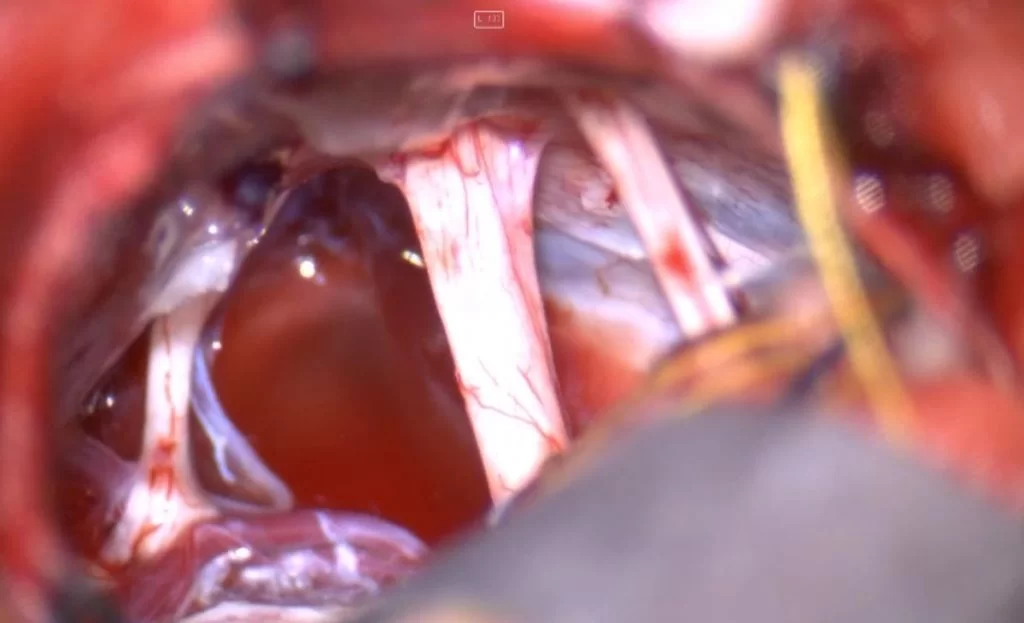

Διενεργήθη οπισθοσιγμοειδική οστεοπλαστική προσπέλαση και ολική εξαίρεση της βλάβης.

Οι επιδερμοειδείς κύστεις είναι απολύτως καλοήθεις όγκοι, οι οποίοι αναπτύσσονται αργά αλλά σταθερά. Το πρόβλημα συχνά είναι ότι τη στιγμή που γίνονται αντιληπτοί έχουν ήδη λάβει μεγάλες διαστάσεις, ενώ μια από τις συνηθέστερες εστίες ανάπτυξής τους -η λεγόμενη γεφυροπαρεγκεφαλιδική γωνία- είναι μια “χειρουργικά απαιτητική” περιοχή της βάσης του κρανίου με πολλά και σημαντικά ανατομικά στοιχεία (δηλαδή με πολλά και σημαντικά νεύρα και αγγεία).

Σε τέτοιες βλάβες είναι εξαιρετικά σημαντική η εμπειρία του νευροχειρουργού στη χειρουργική των όγκων της βάσης κρανίου. Σημαντικά βοηθήματα είναι ο διεγχειρητικός νευροφυσιολογικός έλεγχος και η χρήση του ενδοσκοπίου προκειμένω να ελεγχθούν ακόμα και “κρυφά” σημεία του χειρουργικού πεδίου.